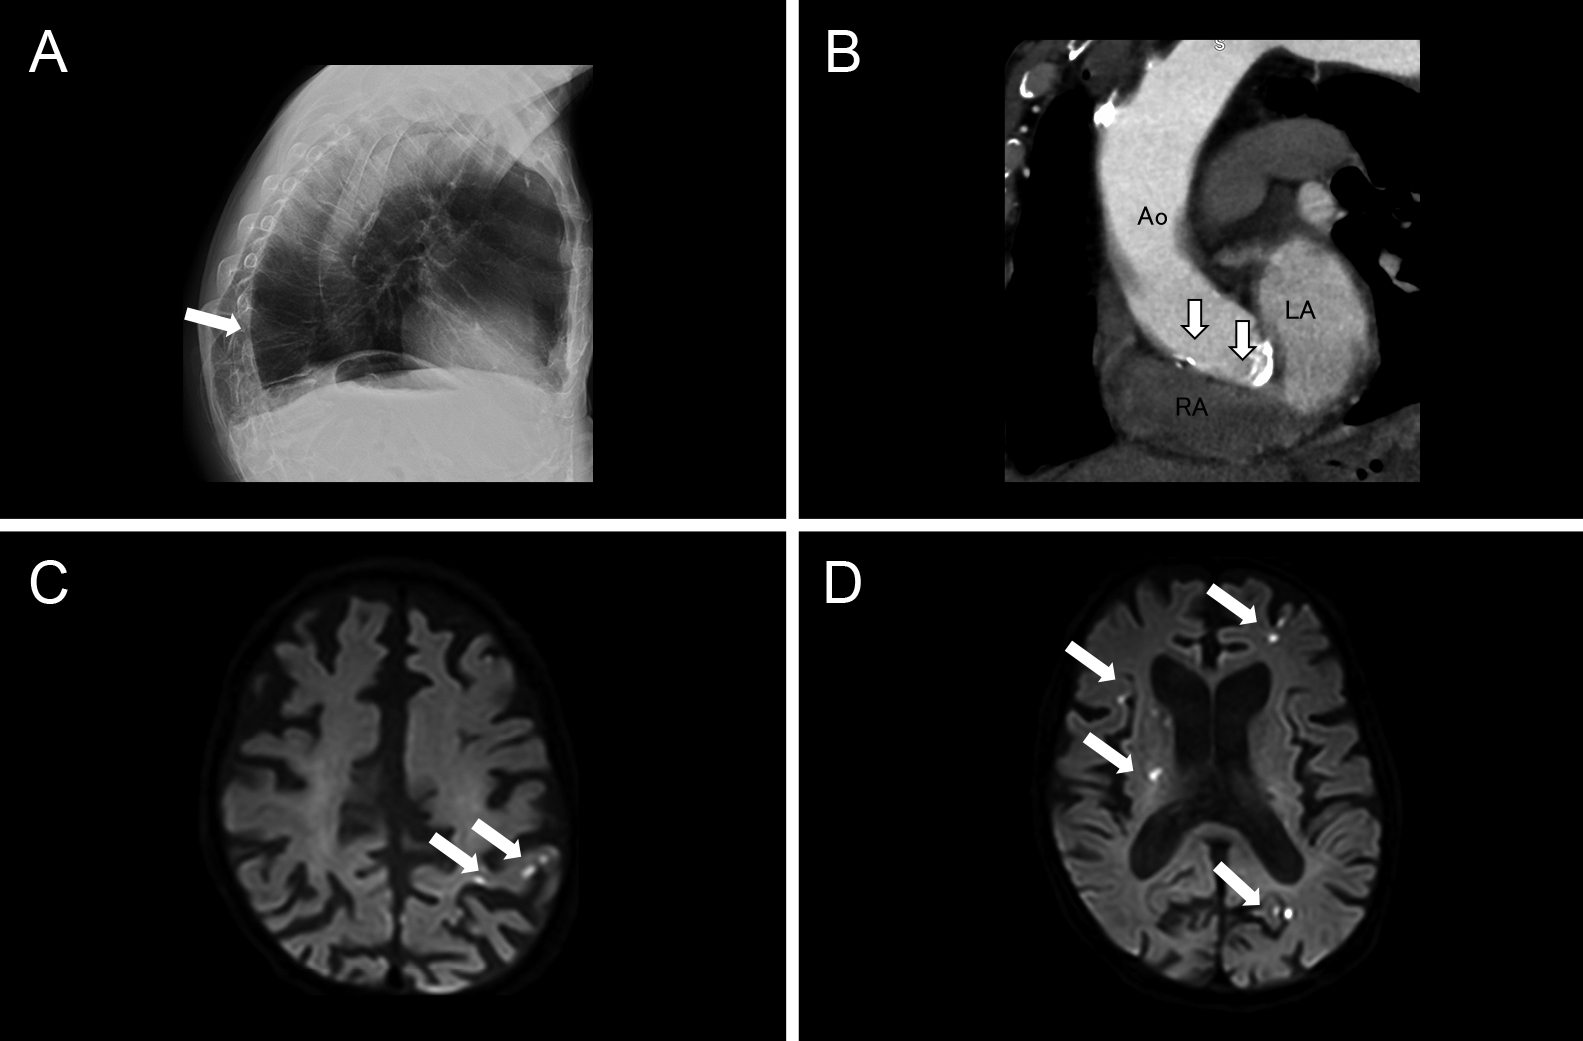

直接経口抗凝固薬内服にもかかわらず脳梗塞を発症した心房細動患者に対する経皮的左心耳閉鎖術:症例報告

Percutaneous left atrial appendage closure for atrial fibrillation-related ischemic stroke despite direct oral anticoagulation: a case report

川端 健新, 江頭 柊平, 村松 恭祐, 逸見 文昭, 宇羽野 恵, 小西 明範, 大森 奈美, 山口 徹雄, 児玉 隆秀, 上坂 義和

Kenshin Kawabata, Shuhei Egashira, Kyosuke Muramatsu, Fumiaki Henmi, Megumi Ubano, Akinori Konishi, Nami Omori, Tetsuo Yamaguchi, Takahide Kodama, Yoshikazu Uesaka

2026/02/13